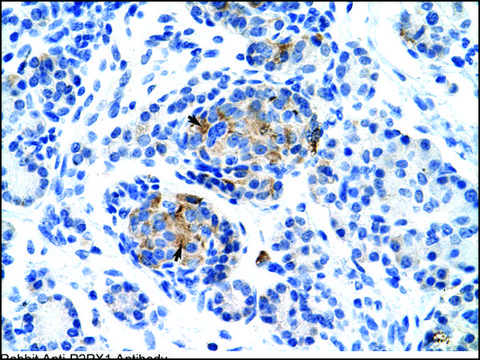

Rabbit Anti-P2RX1 antibody is suitable for western blot (2.5 μg/ml) and IHC (4-8 μg/ml) applications.